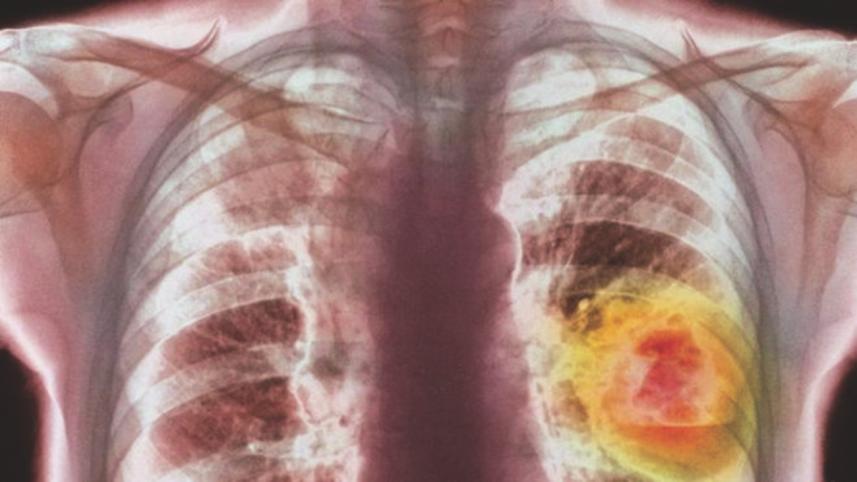

Lung cancer is the most deadly type of cancer, killing nearly 1.6 million people every year. It is hard to treat as it is often diagnosed late and many people with smoking-related diseases are unsuitable for surgery.

The trial, conducted in Europe and the US, was on patients who had advanced lung cancer and who had already tried other treatments. People on standard therapy lived for another 9.4 months at this stage, but those taking Nivolumab lived for 12.2 months on average.